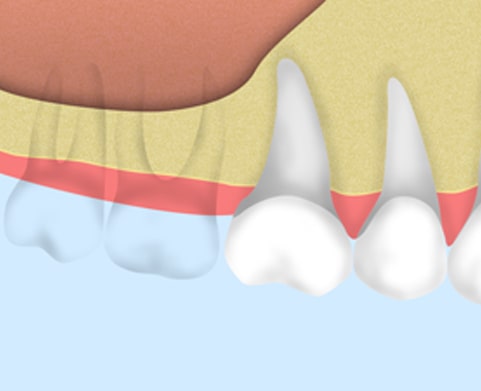

インプラント治療とは、歯を失った箇所に人工の歯根(インプラント)を埋入し、歯を補う治療法です。

骨が薄いままインプラントを埋めると、粘膜を傷つけ炎症を起こしてしまったり、インプラントが安定しない原因となります。